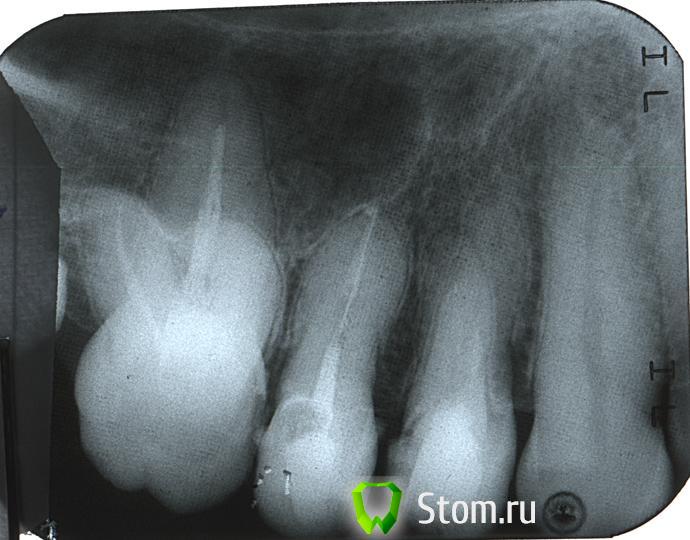

eon Опубликовано 21 ноября, 2011 Поделиться Опубликовано 21 ноября, 2011 Вопрос к уважаемым специалистам.Есть ли на снимке гранулема? Или может быть что-то ещё не так?Зубы не то чтобы болят, но тихонько ноют, какой именно не могу понять (4 или 5-ый). Ссылка на комментарий

Salma Опубликовано 21 ноября, 2011 Поделиться Опубликовано 21 ноября, 2011 Вопрос к уважаемым специалистам.Есть ли на снимке гранулема? Или может быть что-то ещё не так?Зубы не то чтобы болят, но тихонько ноют, какой именно не могу понять (4 или 5-ый).Кажется мне что болит 4–ый, но перелечивать надо и 5 и 6 зуб. Ссылка на комментарий

Sib-oboima Опубликовано 21 ноября, 2011 Поделиться Опубликовано 21 ноября, 2011 по моему боли от 4, по хоже на полость в контакте с 5 у десны Ссылка на комментарий

ннэт Опубликовано 21 ноября, 2011 Поделиться Опубликовано 21 ноября, 2011 Вопрос к уважаемым специалистам.Есть ли на снимке гранулема? Или может быть что-то ещё не так?Зубы не то чтобы болят, но тихонько ноют, какой именно не могу понять (4 или 5-ый).Гранулем пока нет, но если не перелечить 4.5 и 6 тоже -то они обязательно там появятся -вопрос времени.... Ссылка на комментарий